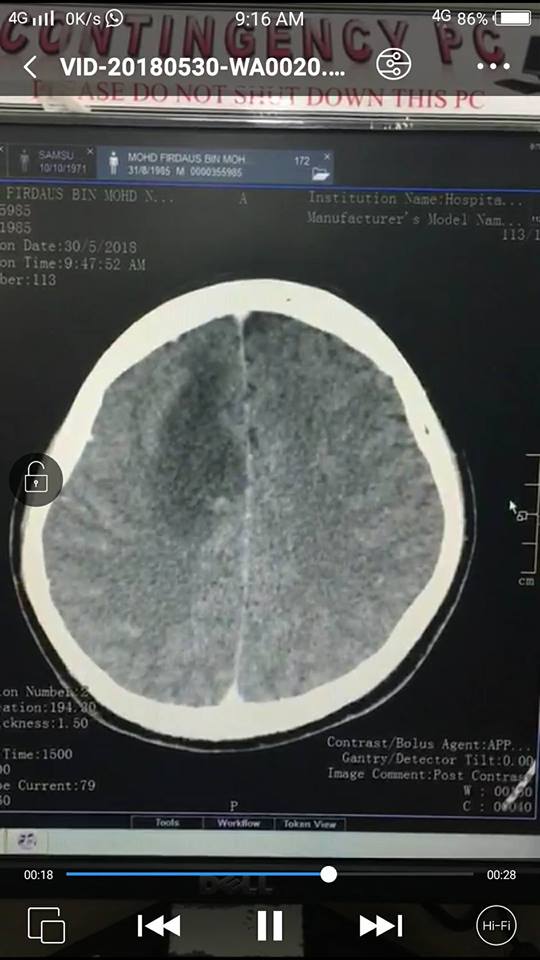

So, pendekkan cerita, di bawah ini adalah gambar CT Scan yang dibuat pada pagi Rabu 30 Mei. Gambar rajah kiri bersamaan otak kanan, yang kanan otak kiri. Selepas habis scan, aku pun baliklah dan tengah hari tadi dapat panggilan dari doktor Hospital Putrajaya (HPJ), suruh datang semula dan terus pergi ke Jabatan Kecemasan, jumpa doktor di bahagian semi kritikal.

Aku pun pelik dan tanya kenapa. Doktor kata, ada nampak ‘sesuatu’ di otak kanan aku bila masuk air contrast CT Scan.